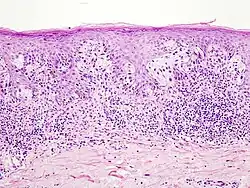

- Окончательный диагноз меланомы может быть установлен только после гистологического исследования, проведённого после тотального удаления невуса (опухоли) с достаточным захватом здоровых тканей. Предоперационная биопсия с помощью иглы или частичного удаления противопоказана, во избежание распространения меланомы. Определяется глубина прорастания (Clark, Breslow) и митотический индекс.